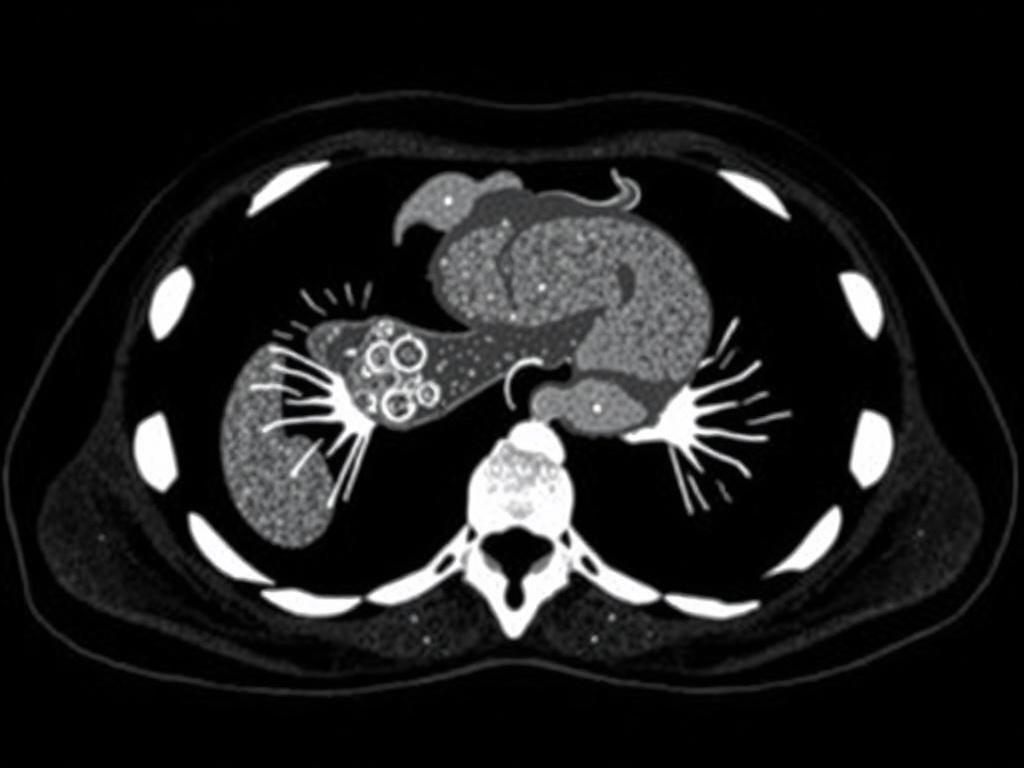

КТ — это серия рентгеновских снимков, получаемых вокруг тела и собранных в объемное изображение. По сути, компьютер-томограф позволяет «резать» печень тонкими срезами и рассматривать каждый участок под разными углами. Для оценки многих поражений важна не только форма и размеры, но и то, как они накапливают контрастное вещество в разные фазы.

Большая часть информативности КТ печени связана с многократным сканированием после внутривенного введения контрастного вещества. Разные фазы показывают разные свойства тканей и сосудов.

Типичный многоп фазный протокол включает сканирование без контраста, затем артериальную, портальную и позднюю фазы. Время начала каждой фазы подбирают с учетом веса и скорости введения препарата.

Для некоторых задач добавляют дополнительные фазы или выполняют реконструкции сосудов. Плотность измеряют в Hounsfield units; изменение плотности между фазами помогает отличить гемангиому, цисту или метастаз.

Типичные находки и как их отличать

Различить образования в печени — это как различать птиц в парке: некоторые отличия заметны сразу, для других требуется внимательный взгляд и опыт. Ниже — ключевые характеристики обычных находок на КТ.

| Гемангиома | Гиперваскулярная, на артериальной фазе центростремительное накапление, на отсроченной фазе равномерное заполнение | Классическая центростремительная динамика, четкие границы |

| Киста | Негомогенная, не накапливает контраст | Нулевая плотность в нативе, отсутствие усиления |

| Метастазы | Разнообразны: гипо- или гиперваскулярные; часто более заметны в портальной фазе | Множественные очаги, разная плотность по фазам |

| Гепатоцеллюлярная карцинома | Гиперваскулярна в артериальной фазе с «отмыванием» в портальной | Артериальное усиление + последующее уменьшение контраста |

Опытный радиолог оценивает не только форму, но и динамику контрастирования, соседние структуры и сосуды. Иногда нужны дополнительные исследования — МРТ с контрастом или биопсия для точного диагноза.